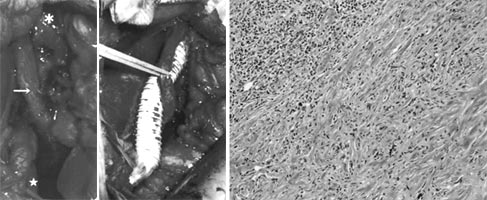

| Fig. 2 |

Operative fidings showed the tumor firmly surrounding

the right iliac vessels and ureter (arrow, A). Venous bypass

was performed between external iliac vein (A) and inferior vena

cava (B) as well as ureterolysis. Pathlogical fidings of the

tumor (C) showed chronic inflammatory cell infiltration consisting

of plasma cells and lymphocytes along with a proliferation of

collagen fibers (hematoxylin eosin stain). |